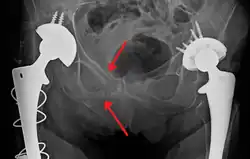

TC abdominal mostrando lesão da artéria renal esquerda

O trauma abdominal contuso (TAB) representa 75% de todos os traumas contusos e é o exemplo mais comum dessa injúria.[4] 75% dos TAB ocorrem em colisões de veículos motorizados,[5] em que a desaceleração rápida pode impulsionar o motorista contra o volante, opainel de bordo ou o cinto de segurança,[6] causando contusões em casos menos graves ou ruptura de órgãos internos nos casos mais graves devido ao rápido aumento da pressão intraluminal, dependendo da força aplicada. Inicialmente, pode haver poucos indícios de que tenha ocorrido lesão abdominal interna grave, tornando a avaliação mais desafiadora e requerendo alto grau de suspeita clínica.[7]

A desaceleração, por outro lado, causa estiramento e cisalhamento nos pontos onde os conteúdos móveis do abdomen, como os intestinos, estão ancorados. Isso pode causar ruptura do mesentério intestinal e lesões nos vasos sanguíneos que passam por ele. São exemplos clássicos desses mecanismos ruptura no fígado por meio de seu ligamento redondo e lesões nas artérias renais.